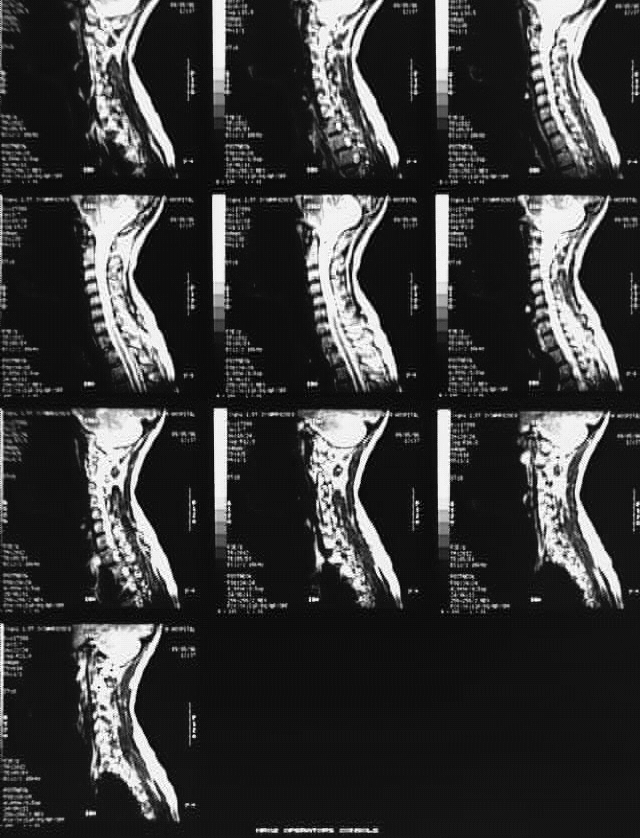

Radiology Images

Head & Neck:Cervical Spine MRI 2: